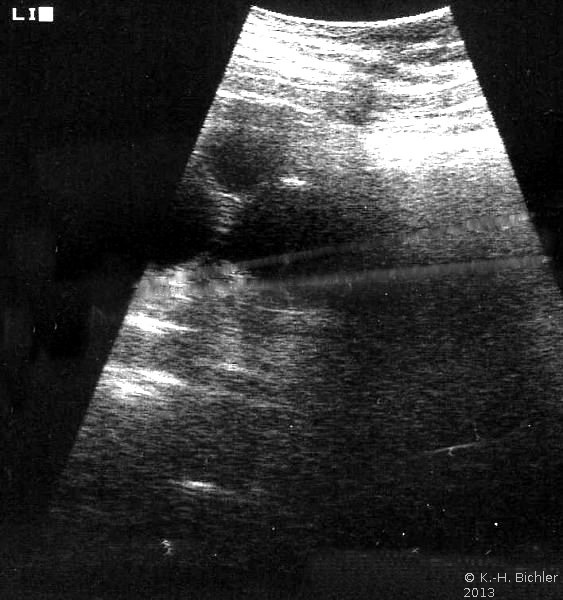

Bei einer 16-jährigen Jugendlichen wurde wegen Flankenschmerzen und sonographischem Verdacht auf einen linksseitigen zystischen Nierentumor die Freilegung durchgeführt (Abbildung 3). Dabei fand sich ein zystischer Tumor (Abbildung 4). Die histologische Untersuchung ergab eine multizystische, dysplastische Nierendegeneration.

Da die unilaterale multizystische Nierendysplasie nicht immer vergrößert ist, fallen derartige Tumoren unter Umständen erst im Erwachsenenalter anlässlich Untersuchungen aufgrund anderer Erkrankungen auf. Die Organe werden zumeist wegen der Differentialdiagnose zum zystischen Nierenzellkarzinom entfernt.